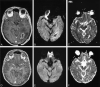

Fig 3.

Patient 2. A 31-year-old man with fever, seizures, and weakness of the left upper extremity. DW images were superior to conventional MR images showing re-accumulation of pus and well correlated with increased CRP levels and WBC counts. A–C, Axial contrast-enhanced T1-weighted shows a peripheral enhancing lesion with a hypointense center in the right parietal region. Hyperintensity at DW imaging (B) and a low ADC (C) suggest abscess formation with restricted diffusion due to pus. D–F, One day after surgery, images show decreased size of the abscess (D), hypointensity at DW imaging (E), and a high ADC of 2.56 × 10 −3mm 2/s (F).